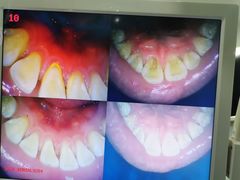

• 土豆口腔(凤凰北总店)

• -土豆口腔(凤凰北总店)

匿名用户 | 22-11-06